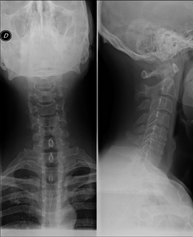

- RX Columna cervical

Tècnica que usa els raigs X a través de la qual s'obtenen imatges de la columna cervical per al seu estudi. Indicacions: traumatisme, dolor cervical. - RX Columna dorsal

Tècnica que usa els raigs X a través de la qual s'obtenen imatges de la columna cervical per al seu estudi. Indicacions: traumatisme, contractura cervical, dolor articular. - RX Ossos propis nasals